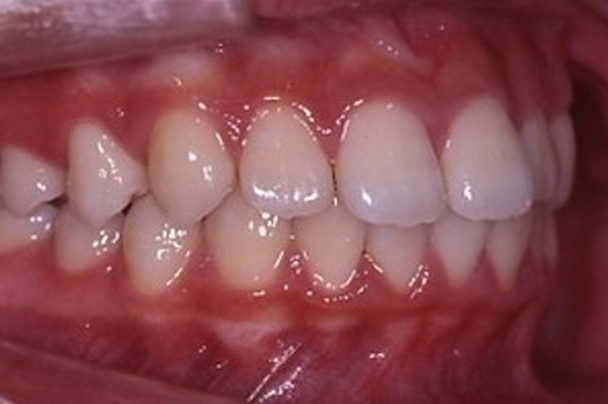

治療後

1年10か月が経過し、下あごが正常な位置まで成長し、出っ歯が解消しました。また過蓋咬合も改善し、下の前歯で上あごの粘膜を咬むことはなくなりました。下あごの成長が期待できるのは「身長がのびている間」に限られていますので、早めに対処することで、あごの成長を用いた治療を行うことができました。矯正治療前は、13歳頃から「抜歯矯正(永久歯を4本抜歯してならべる矯正治療)」になるかもしれないとの説明をしていましたが、このまま下あごの位置が落ち着けば、仕上げの治療(マルチブラケット治療)は不要になるかもしれません。